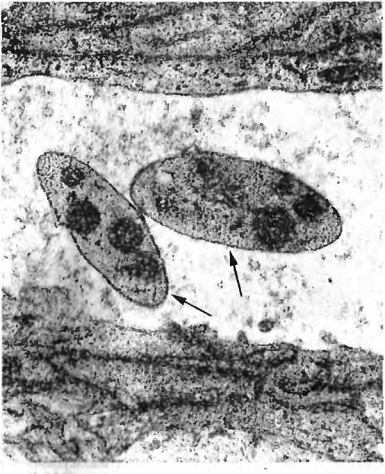

Могут быть нитевидной, шаровидной, овоидной или гантелевилной формы. В мазках-отпечатках окрашиваются по Романовскому — Гимзе в синеватый цвет (цв. рис. 14), размножаются простым делением. На электроно- грамме (рис. 23) видны риккетсии в просвете капилляра.Поражается преимущественно крупный рогатый скот в возрасте от двух дней до года, взрослые болеют реже и риккетсиоз глаз у них протекает легче. Могут заражаться овцы, козы и свиньи. Болезнь часто принимает характер энзоотии или эпизоотии. Регистрируют круглый год. У крупного рогатого скота кроме поражения глаз риккетсии вызываиот пневмонии, эндометриты, маститы, аборты, артриты, орхиты, тендовагиниты (Л. Д. Тимченко, О. А. Са- пожкова, Г. П. Пигарева).

Рис. 23. Rickettsia conjunctivae bovis (показаны стрелками) в просвете капилляра. Электрограмма (по В. А. Черваневу)